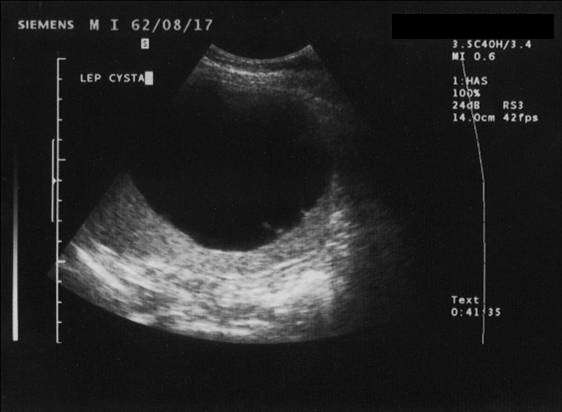

The simple cyst (Figure 16) indicates a difference from the multicystic liver only in the number of the cysts. Conversely, the polycystic liver (Figure 17) is an autosomal dominant inheritant disorder, in which the cystic conversion can be present in up to 70-80% of the liver parenchyma due to the large number of the cysts. It often accompanies with polycystic kidneys, whilst the entire polycystic syndrome – if also polycystic affection of the pancreas is also associated – occurs very rarely.

Figure 16: Simple liver cyst, US

Differentialdiagnostic difficulty is only given if the liver cysts show atypical appearence (its content becomes more hyperechogenic in US or more hyperdense in CT). In this situation, the differentiation from cystic tumor, metastasis or probably abscess is possible only if taking into account the clinical data and performing US or CT-guided punction.

MRI image shows a smooth contour characteristic to the cysts, which has low signal intensity on T1 and very high signal intensity on T2-weighted images. In case of a complicated cyst (fibrosis, condensation, hemorrhagia) various MRI signal intensities can be observed according to the complications.